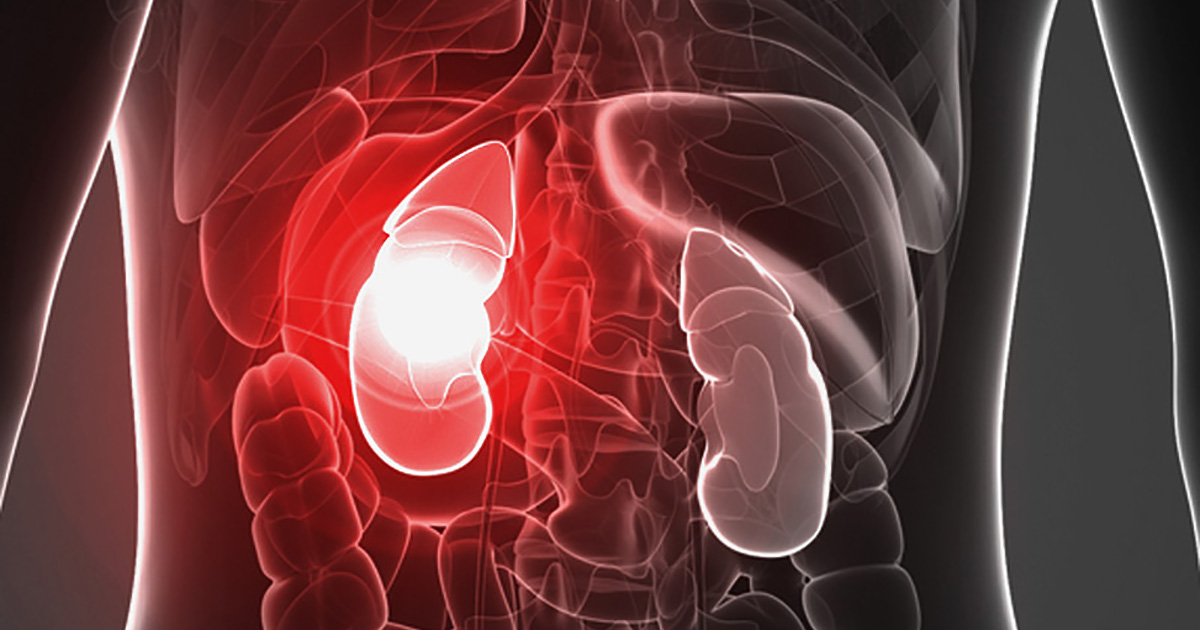

Kidney failure occurs when the kidneys are no longer able to function well enough for a person to survive without dialysis or a kidney transplant. Though the condition often progresses slowly, chronic kidney disease eventually leads to kidney failure. There is no cure, but those who receive dialysis, or a transplant, often live for many years. There are indications that CBD manages symptoms of kidney disease, such as inflammation and chronic pain.

Several health conditions can lead to chronic kidney disease and, eventually, failure. These conditions damage the kidneys, reducing their ability to filter the body’s waste. When the organs don’t function correctly, waste and toxins accumulate in the body.

Diabetes causes kidney failure more often than any other condition, but other types of kidney failure include those caused by autoimmune diseases, high blood pressure and genetic diseases. The symptoms of kidney failure are similar to those of chronic kidney disease, though more severe. Chronic inflammation and pain are common. Other symptoms include: